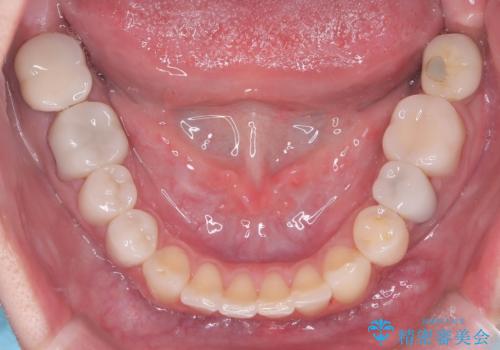

治療が進むにつれ、突出していた八重歯がスムーズに列に収まり、凹凸がなくなったことで、以前よりもブラッシングがしやすく清潔な口腔環境が整いました。治療完了後、長年のコンプレックスから解放された患者様の笑顔は非常に明るく、40代からでも遅くない「大人の矯正」の大きなメリットを実感していただける症例となりました。